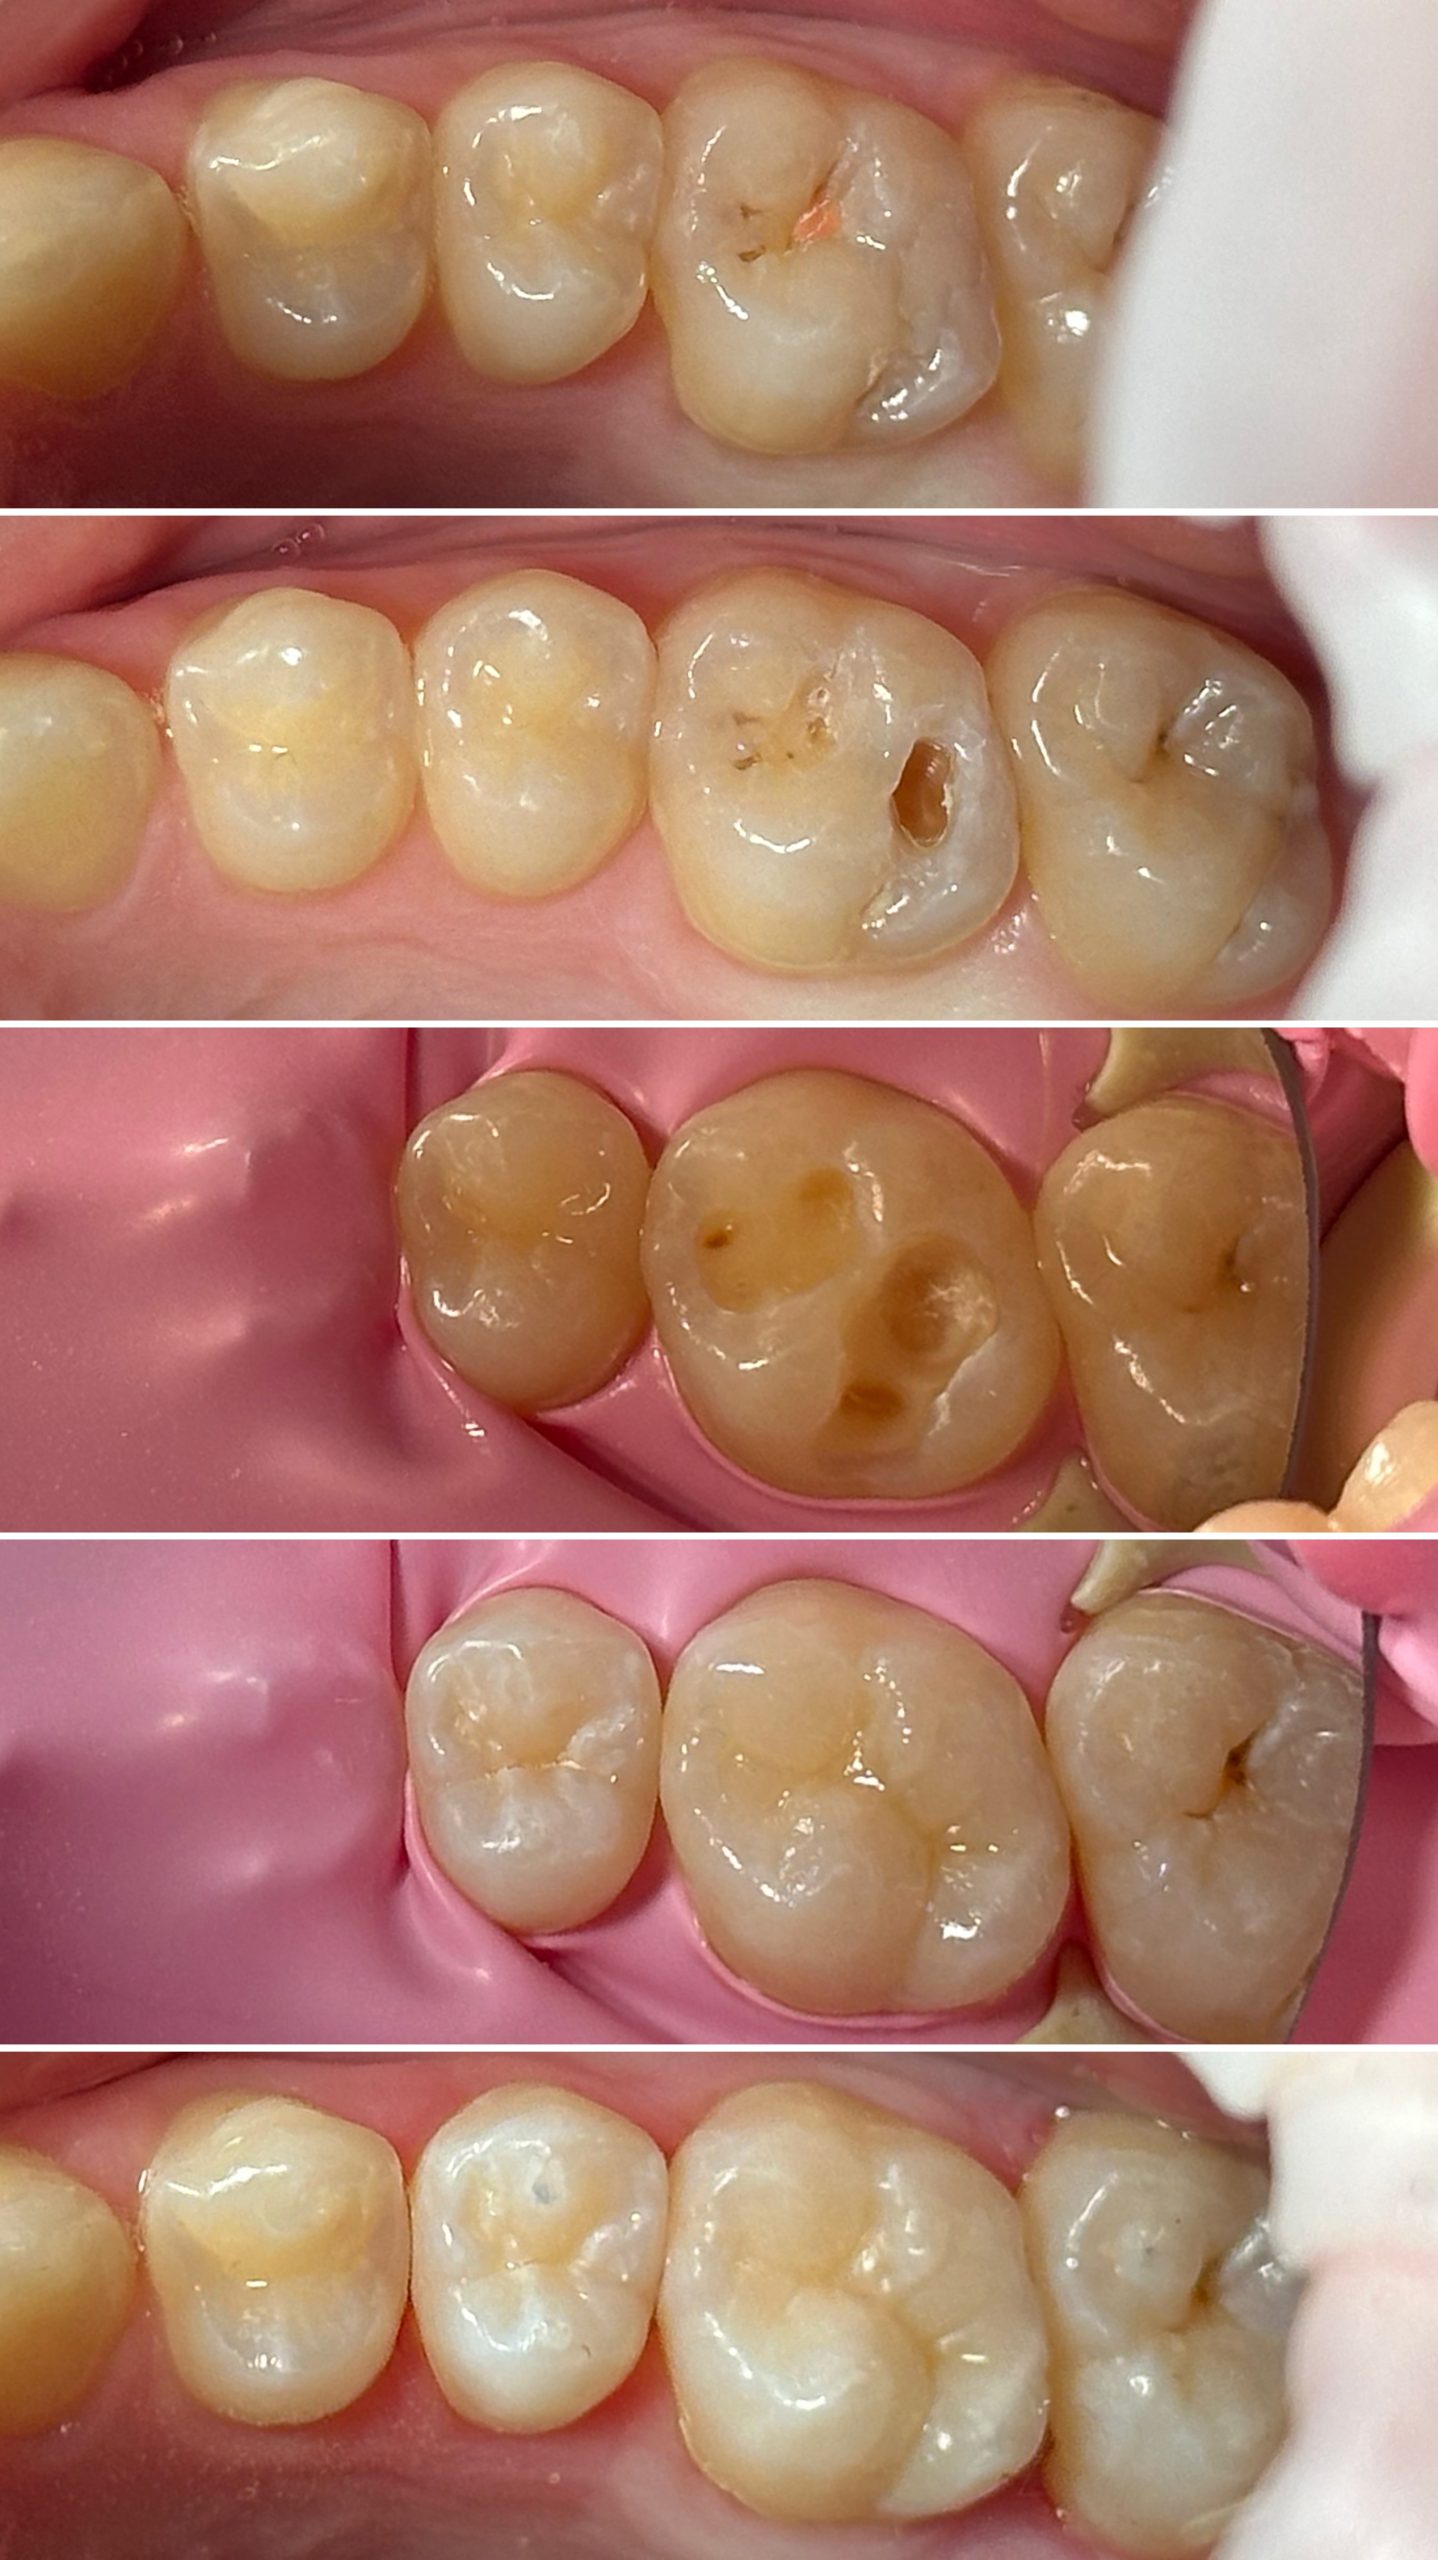

• Диагностика и лечение кариеса и его осложнений (пульпиты, периодонтиты)

• Художественная реставрация фронтального и бокового участка зубов

2022 год – «Прямая реставрация.Боковой сегмент.» Игорь Гудыма